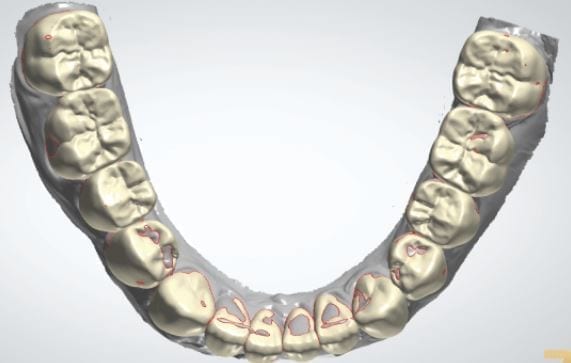

Over the course of a few appointments, the vertical dimension was reduced and the temporaries were adjusted to the patient’s desires. The new upper and lower arch were captured with the Medit i500 and the jaws were related to each other.

This was then imported into exocad where the prepped arches from a few weeks prior were force matched to the new bite

After the upper jaw was related to the temps, the same was done with the lower arch. Great care was taken to make sure the arches were properly related to each other throughout the process

The case was designed by CADENT BESSA, and the models were printed by Burbank Dental Lab with Carbon Printers. There restorations were milled and cut back and layered by Burbank Dental Lab